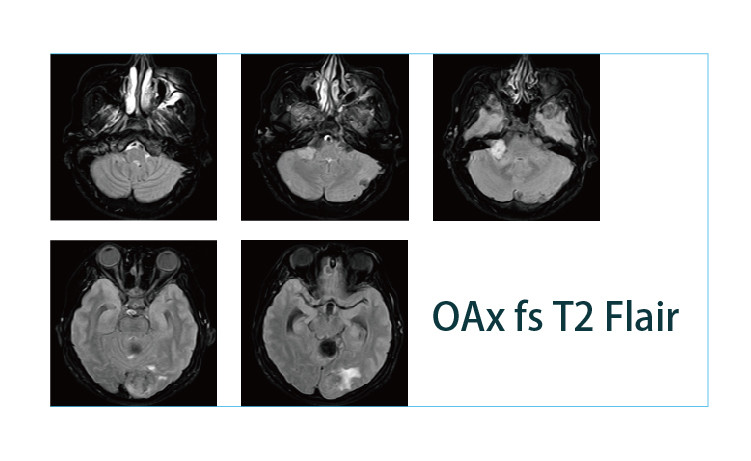

【朗润影像档案】磁共振影像病例分享(编号20190412)